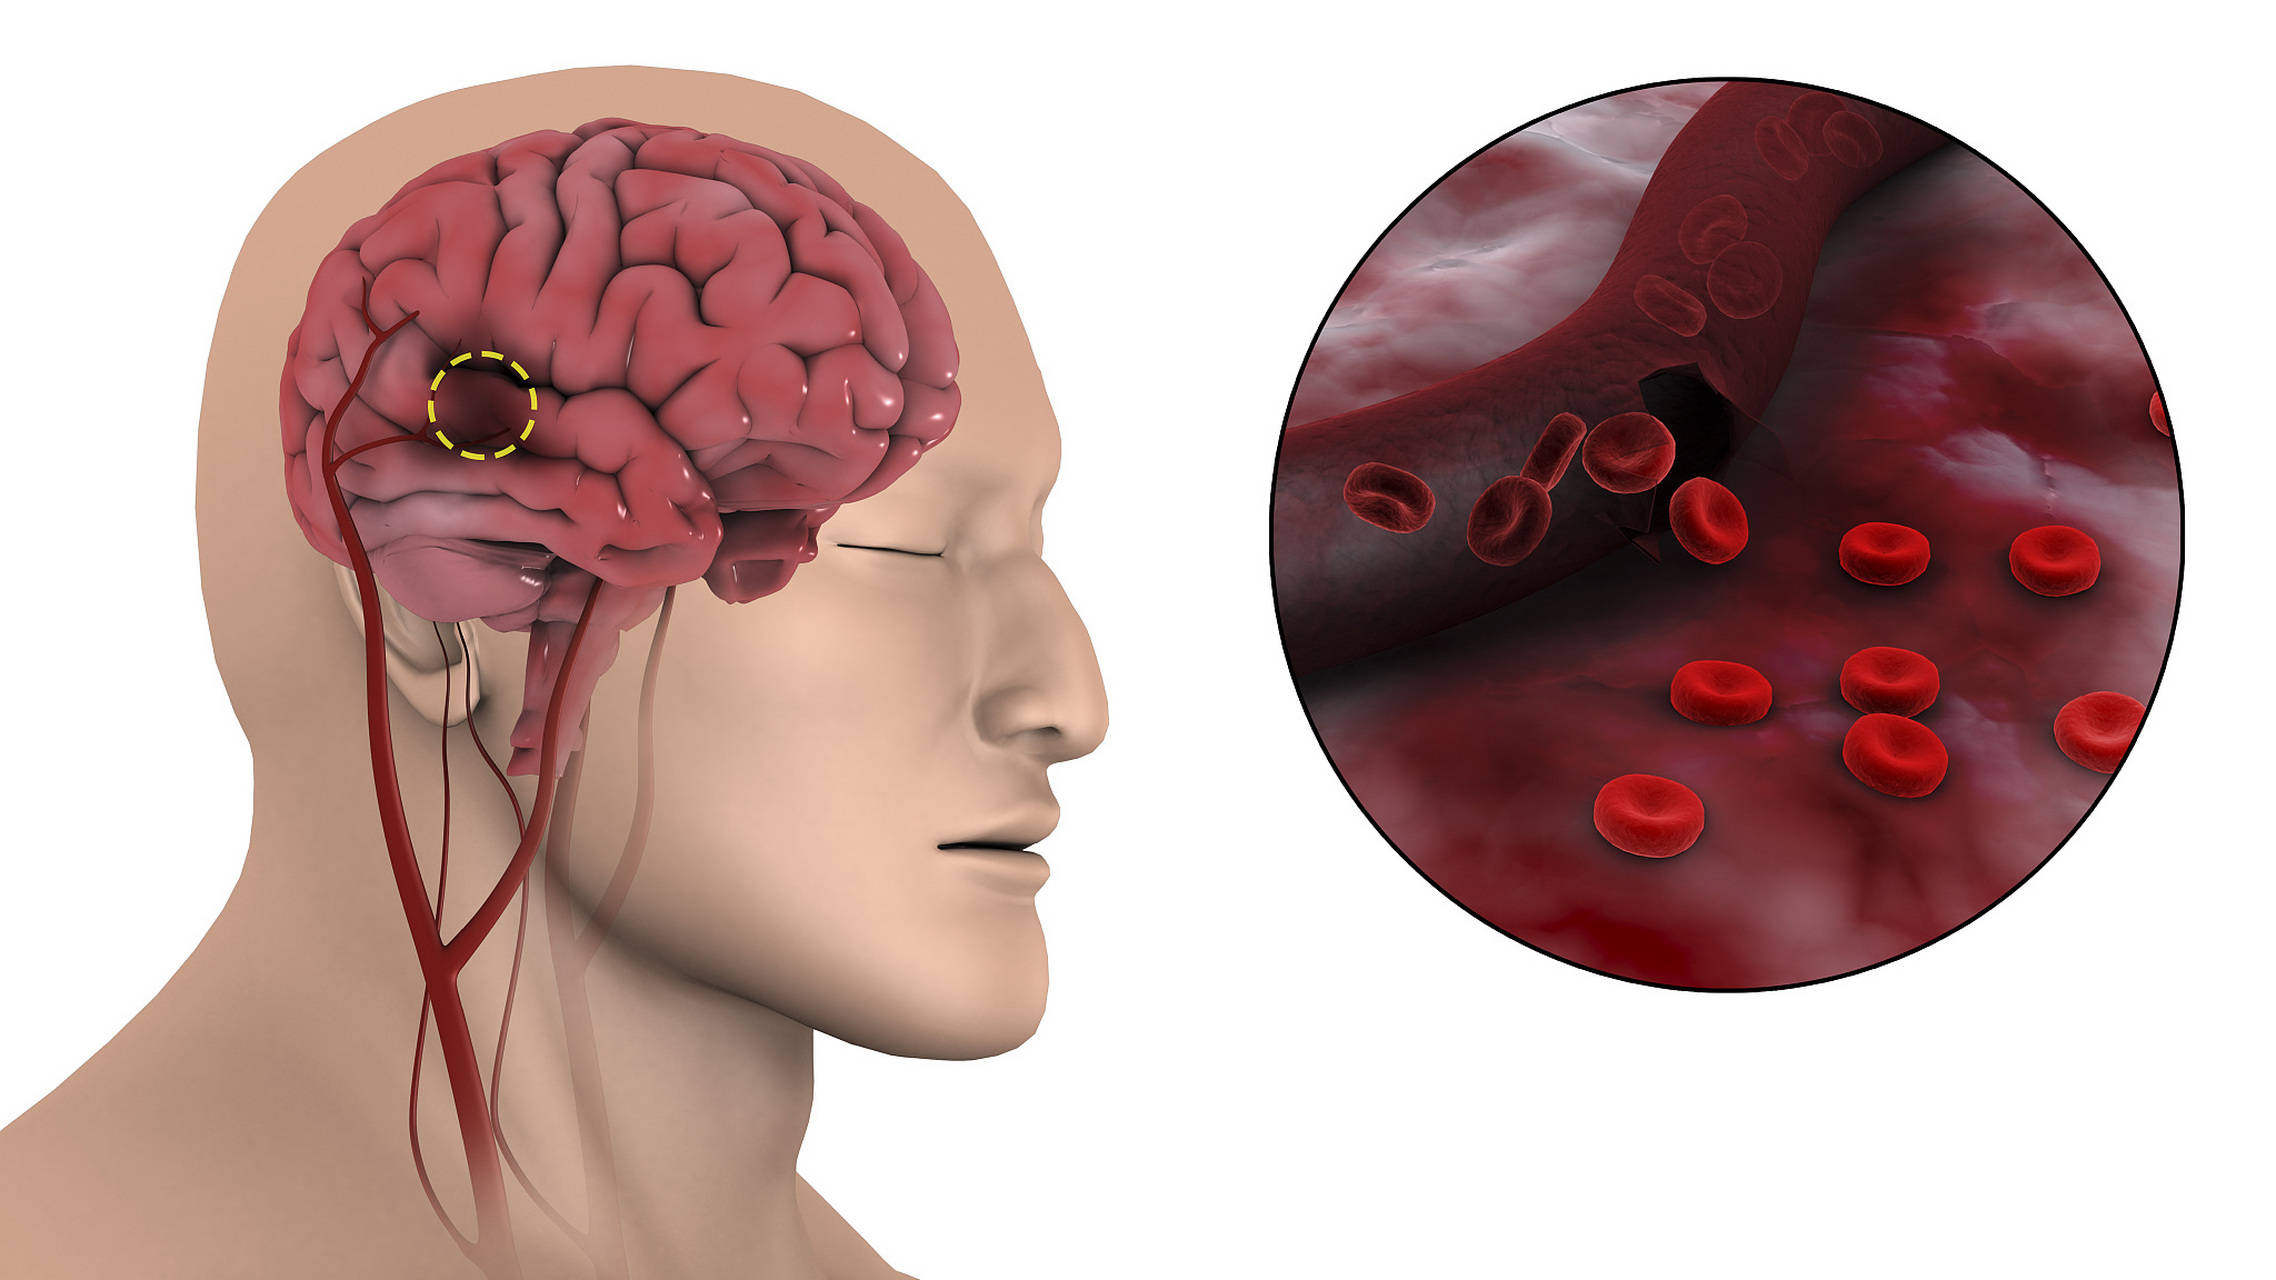

颈动脉,这条藏在脖子两侧的“生命通道”,负责向大脑输送近八成的血液。一旦它出问题,后果远比你想象的严重。你以为脑梗是突然发生的?错!它往往悄悄酝酿数年,而体检中的那一行小字,就是风暴来临前的微风。

还有一种常见误解:只要没症状,就不需要干预。大错特错!医学研究明确指出,无症状颈动脉狭窄超过50%,未来五年内发生脑梗的风险高达10%以上。这不是危言耸听,而是冰冷的数据。

那怎么判断自己有没有风险?除了体检报告,还可以关注几个“蛛丝马迹”:比如早晨起床后手指发麻持续几分钟;看东西偶尔出现短暂黑影;走路时突然失去平衡感。这些短暂性脑缺血发作(TIA),其实是身体在拉响警报。

可是接下来的一幕让众人都目瞪口呆:一位45岁的企业高管,体检显示颈动脉斑块70%狭窄,医生建议药物+生活方式干预。他却说“我忙着呢,等年底再说”。三个月后,他在会议室突发失语,送医确诊为大面积脑梗。拖延,是最昂贵的医疗选择。